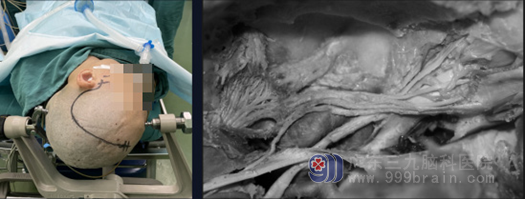

图 3 扩大的中颅窝底入路切口,解剖示去除硬膜后中颅窝底的神经结构。

经颞下入路,右侧卧位,显微镜下沿硬膜外分离,保护岩浅大神经,磨除岩尖。从颞底切开硬膜见三叉神经半月节内肿瘤,质软,灰褐色,肿瘤无包膜,肿瘤向前侵入海绵窦,向后下暴露脑干、滑车神经、面听神经、外展神经和后颅窝,大部分切除肿瘤。